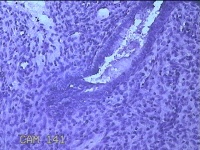

性别

女

年龄

41岁

临床诊断

异常子宫出血;取出子宫内节育器;子宫内膜炎

一般病史

阴道不规则流血2个月。

标本名称

宫腔内容物

大体所见

灰白暗红色不规则碎组织3.5x2.5x0.8cm一堆。